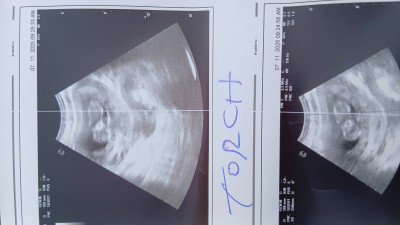

Ultrason sonucu cinsiyet tahmini yapar mısınız

Gebelik haftası 12

Erkeğe benziyor hala belli değilmi ben 11 haftada öğrendim devlette

Erkek bebek 💙